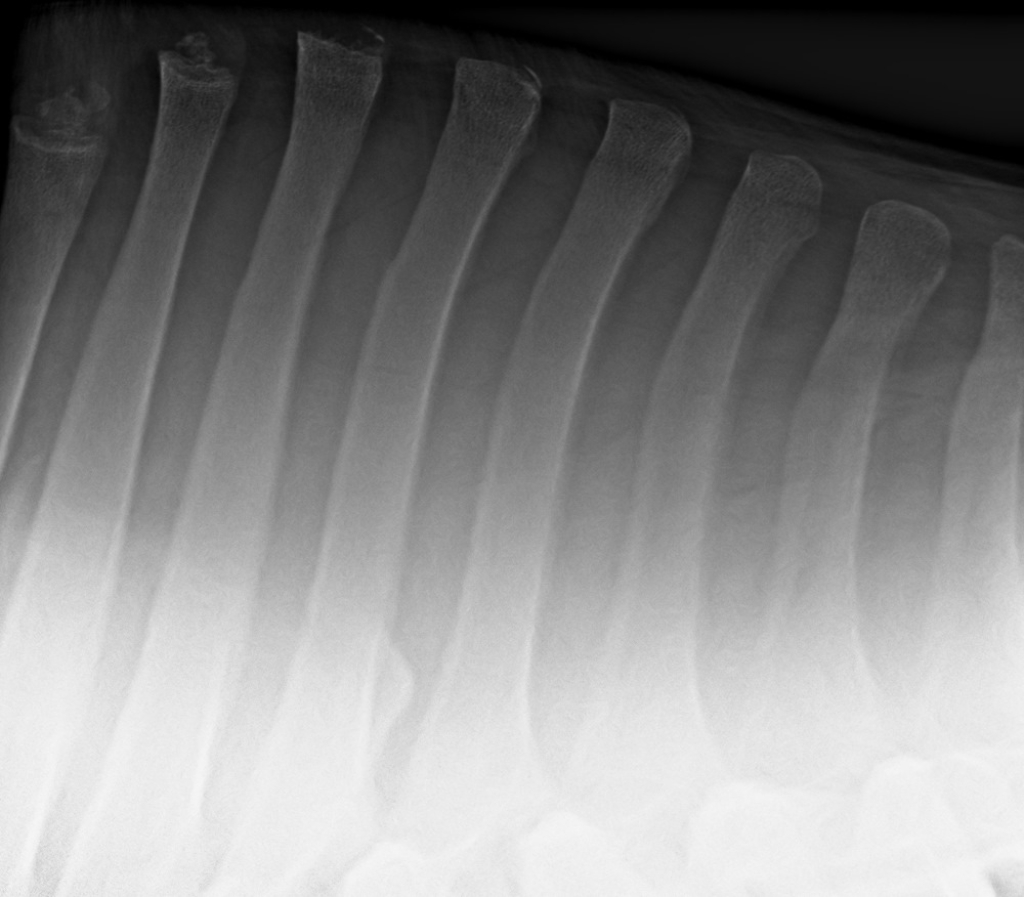

Foto: Röntgenfoto van de doornuitsteeksels van de schoft

Röntgenfoto van de doornuitsteeksels van de schoft

De diagnose van een acute supraspinaal ligament blessure is vaak op basis van het klinisch onderzoek en een echografisch onderzoek vrij snel te stellen. Bij ernstigere blessures is het soms noodzakelijk om röntgenopnames van de doornuitsteeksels te maken. Dit in verband met mogelijke blessures van de aanhechting op het bot of breuken van de doornuitsteeksels.